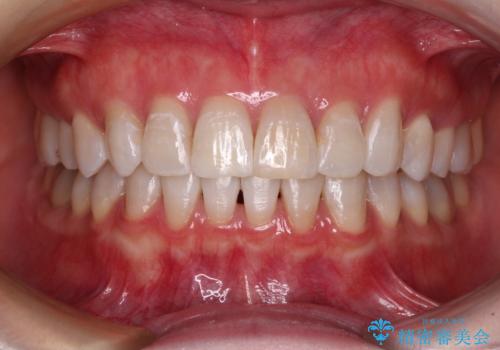

デコボコを治したい インビザラインによる矯正治療

- 前歯のデコボコを気にして来院された患者様です。

前歯が90度近く捻れていたため、しっかりと治すことを考えるとワイヤー矯正の方がおすすめではありましたが、本人の希望によりインビザラインを用いて矯正治療を行うこととしました。

途中2年強の来院がなく、改善されていたデコボコが元に戻ったり、装着時間が不足しており前歯のデコボコは十分に改善することはできませんでしたが、5年間の有効期限内で可能な限り歯列を整えることができました。